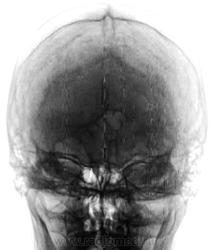

Пол пациента: Женский пол Тип патологии: Другое Область исследования: Скелетно-мышечная система Методы исследования: Rg Какие мнения будут по поводу толщины костей мозгового черепа? https://radiomed.ru/sites/default/files/styles/case_slider_image/public/user/12/2.201201010022_0.jpg?itok=FOwbpyI0 https://radiomed.ru/sites/default/files/styles/case_slider_image/public/user/12/3.201201010024_0.jpg?itok=NW_LOOMI https://radiomed.ru/sites/default/files/styles/case_slider_image/public/user/12/4.201201010026.jpg?itok=JftmY5qZ ID:34651 Чт, 09/01/2014 - 19:24 #1 maker4ik Не на сайте Был на сайте: 8 лет 7 месяцев назад Зарегистрирован: 19.10.2011 - 17:49 Публикации: 2682 Приняли форму извилины? Чт, 09/01/2014 - 20:35 #2 Dima Не на сайте Был на сайте: 7 лет 2 месяцев назад Зарегистрирован: 05.08.2012 - 17:39 Публикации: 2467 Диффузный гиперостоз? Терпимость - это когда прощают чужие ошибки; такт - когда не замечают их. (Артур Шницлер) Чт, 09/01/2014 - 20:49 #3 И.Бондаренко Не на сайте Был на сайте: 1 день 5 часов назад Зарегистрирован: 13.09.2011 - 22:55 Публикации: 9206 В практике встречал один раз. Сделал просто описательную картину. Но там были расширены диплоические каналы. Чт, 09/01/2014 - 21:17 #4 Nela Не на сайте Был на сайте: 6 лет 1 месяц назад Зарегистрирован: 12.05.2009 - 20:43 Публикации: 1847 Вы не указали возраст. Возможно возрастные изменения костей черепа. Пт, 10/01/2014 - 10:21 #5 Катенёв Валенти... Не на сайте Был на сайте: 7 лет 3 недели назад Зарегистрирован: 22.03.2008 - 22:15 Публикации: 54876 Возраст - около 60 лет Пт, 10/01/2014 - 19:31 #6 Nela Не на сайте Был на сайте: 6 лет 1 месяц назад Зарегистрирован: 12.05.2009 - 20:43 Публикации: 1847 Для старческих изменений молода еще. Вероятно дисгормональные.

Приняли форму извилины?

Диффузный гиперостоз?

В практике встречал один раз. Сделал просто описательную картину. Но там были расширены диплоические каналы.

Вы не указали возраст. Возможно возрастные изменения костей черепа.

Возраст - около 60 лет

Для старческих изменений молода еще. Вероятно дисгормональные.